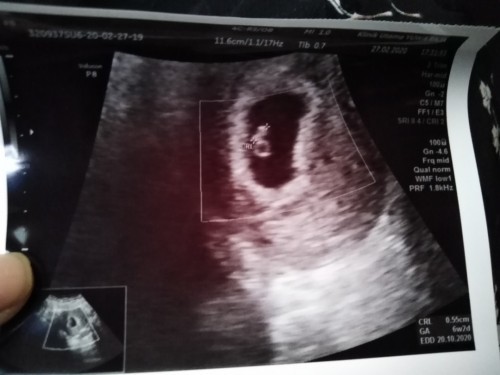

usia kehamilan brp minggu bunda2 USG terlihat janin ny?

6week Alhamdulillah udah keliatan janinnya🥰

6w3d sudah ada janin dan djj nya Alhamdulillah

6 minggu sudah keliatan aku~ usg transvaginal